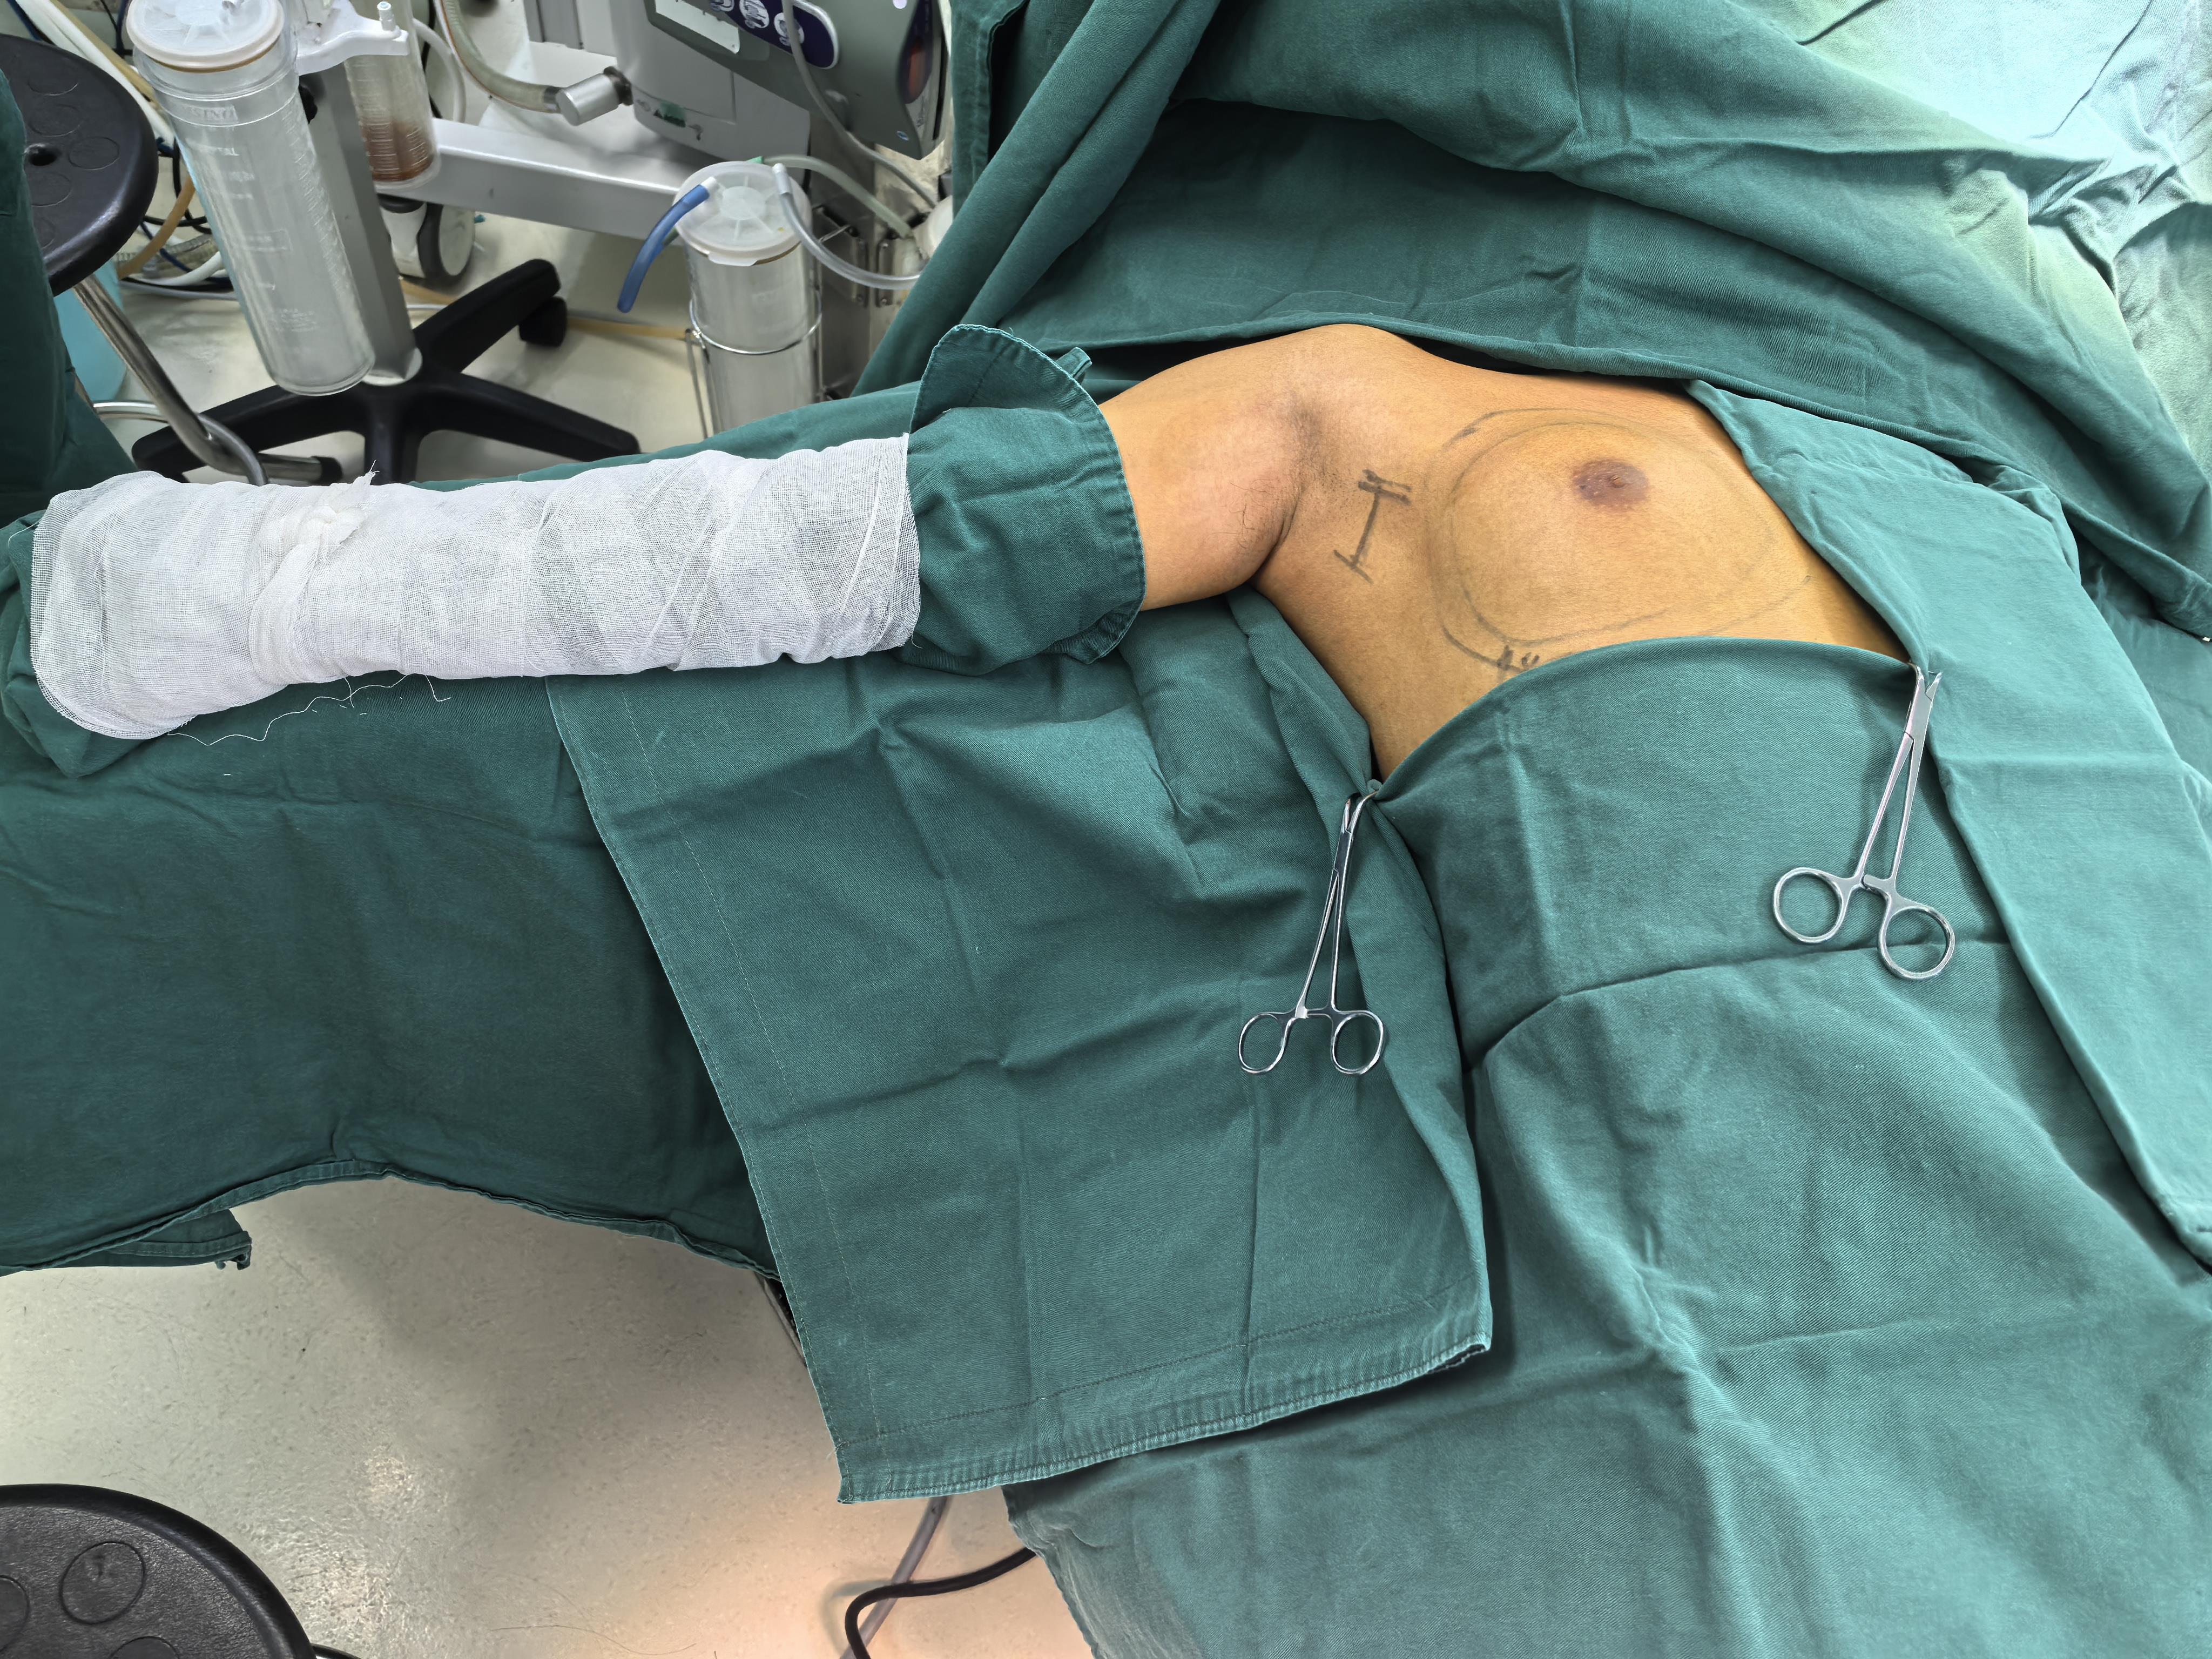

周文斌,王丹丹,潘红,石靓,夏添松,梁燕,马丹丹,王水,齐晓伟,丁强

2026, 35(2):350-356. doi: 10.7659/j.issn.1005-6947.250280

摘要:传统开放乳房全切术创伤大且瘢痕明显,影响患者身心健康及生活质量。随着微创技术的发展,单孔腔镜辅助腋窝入路乳房皮下腺体切除术因切口隐蔽、美观性佳而逐渐受到关注。在此基础上,笔者团队开展了腔镜电剪刀辅助腋窝入路乳房皮下腺体切除术,并在临床实践中不断优化操作流程。该技术以腔镜电剪刀为主要分离工具,结合膨胀液辅助及标准化解剖层次,能够减少皮瓣热损伤,改善术野暴露并提高手术操作的精细度与安全性,同时具有学习曲线相对较短、易于掌握等特点。本文基于200余例手术经验,对术前准备、器械配置、手术步骤及关键操作要点进行系统总结,以期为乳腺外科微创手术的规范化开展提供参考。